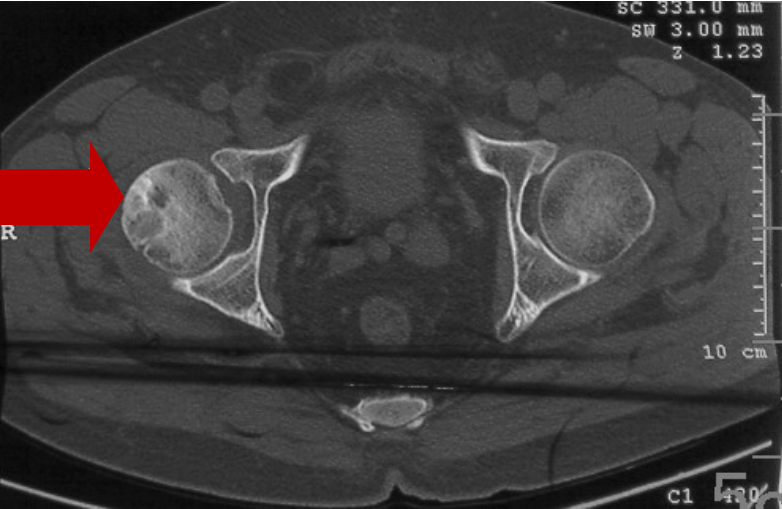

2008年10月21日CT显示:

右股骨头坏死二期